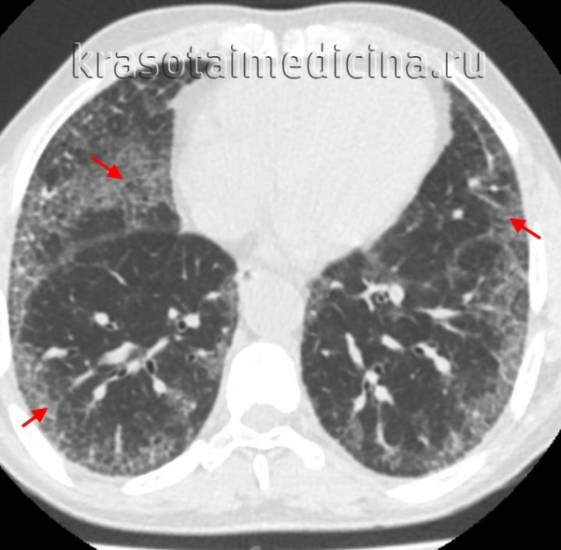

- КТ высокого разрешения. Помогает уточнить распространенность поражения легочной ткани, оценить стадию, активность и темпы прогрессирования фиброзного процесса.

КТ ОГК. Интерстициальная пневмония, участки «матового стекла» (красная стрелка) и ретикулярные изменения.

- Томографическое исследование дает более точные диагностические данные, чем рентгенография, оценивает строение легких и их способность к расправлению, выявляет признаки воспаления межуточной ткани, распространенность поражения, стадию, активность и темпы прогрессирования фиброзного процесса. На снимке видны очаги уплотнения ткани, снижение прозрачности паренхимы легких по типу матового стекла, сегментарные расширения бронхов – бронхоэктазы.